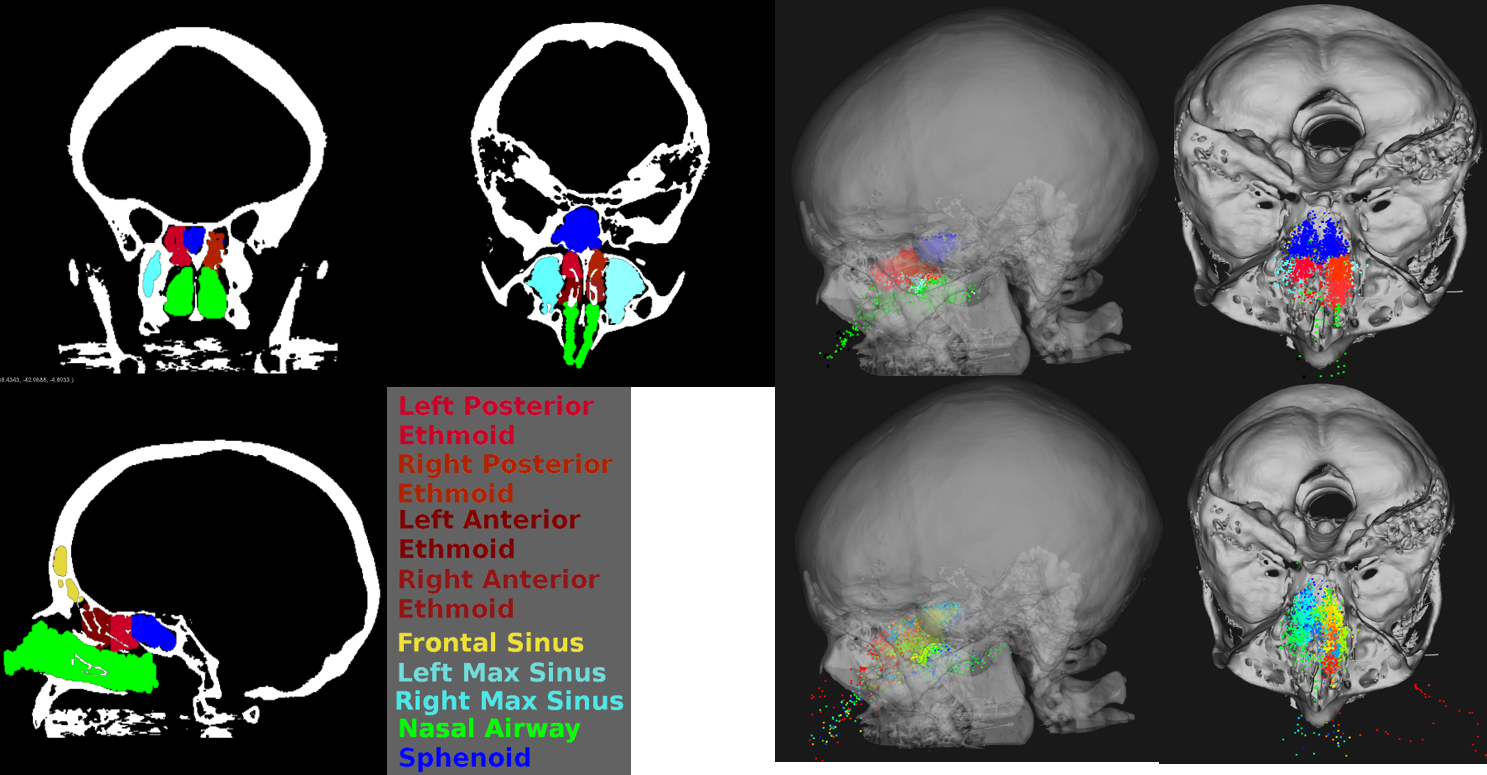

Anatomical Regions for Motion Pattern Study.

We found the motion patterns vary with respect to anatomical tissues, which can be approximated by anatomical regions. Anatomical regions can be reliably automatically segmented, which fundamentally decreases the difficulty of study motion patterns.